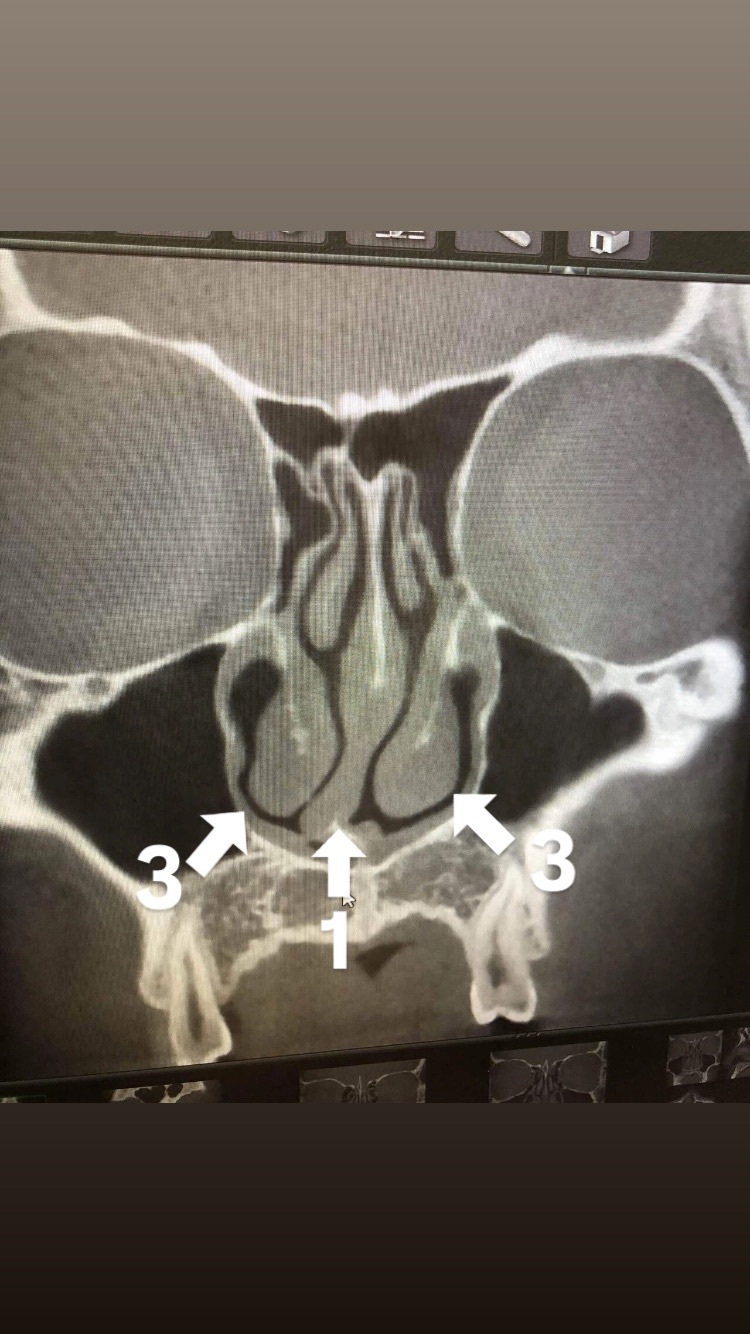

術前の写真

1、鼻中隔軟膏(鼻先の骨、鼻整形もこの部分をいじります)

2、空気の通り道(片鼻は塞がっている状態です)

3、粘膜(アレルギー性鼻炎で腫れてます)